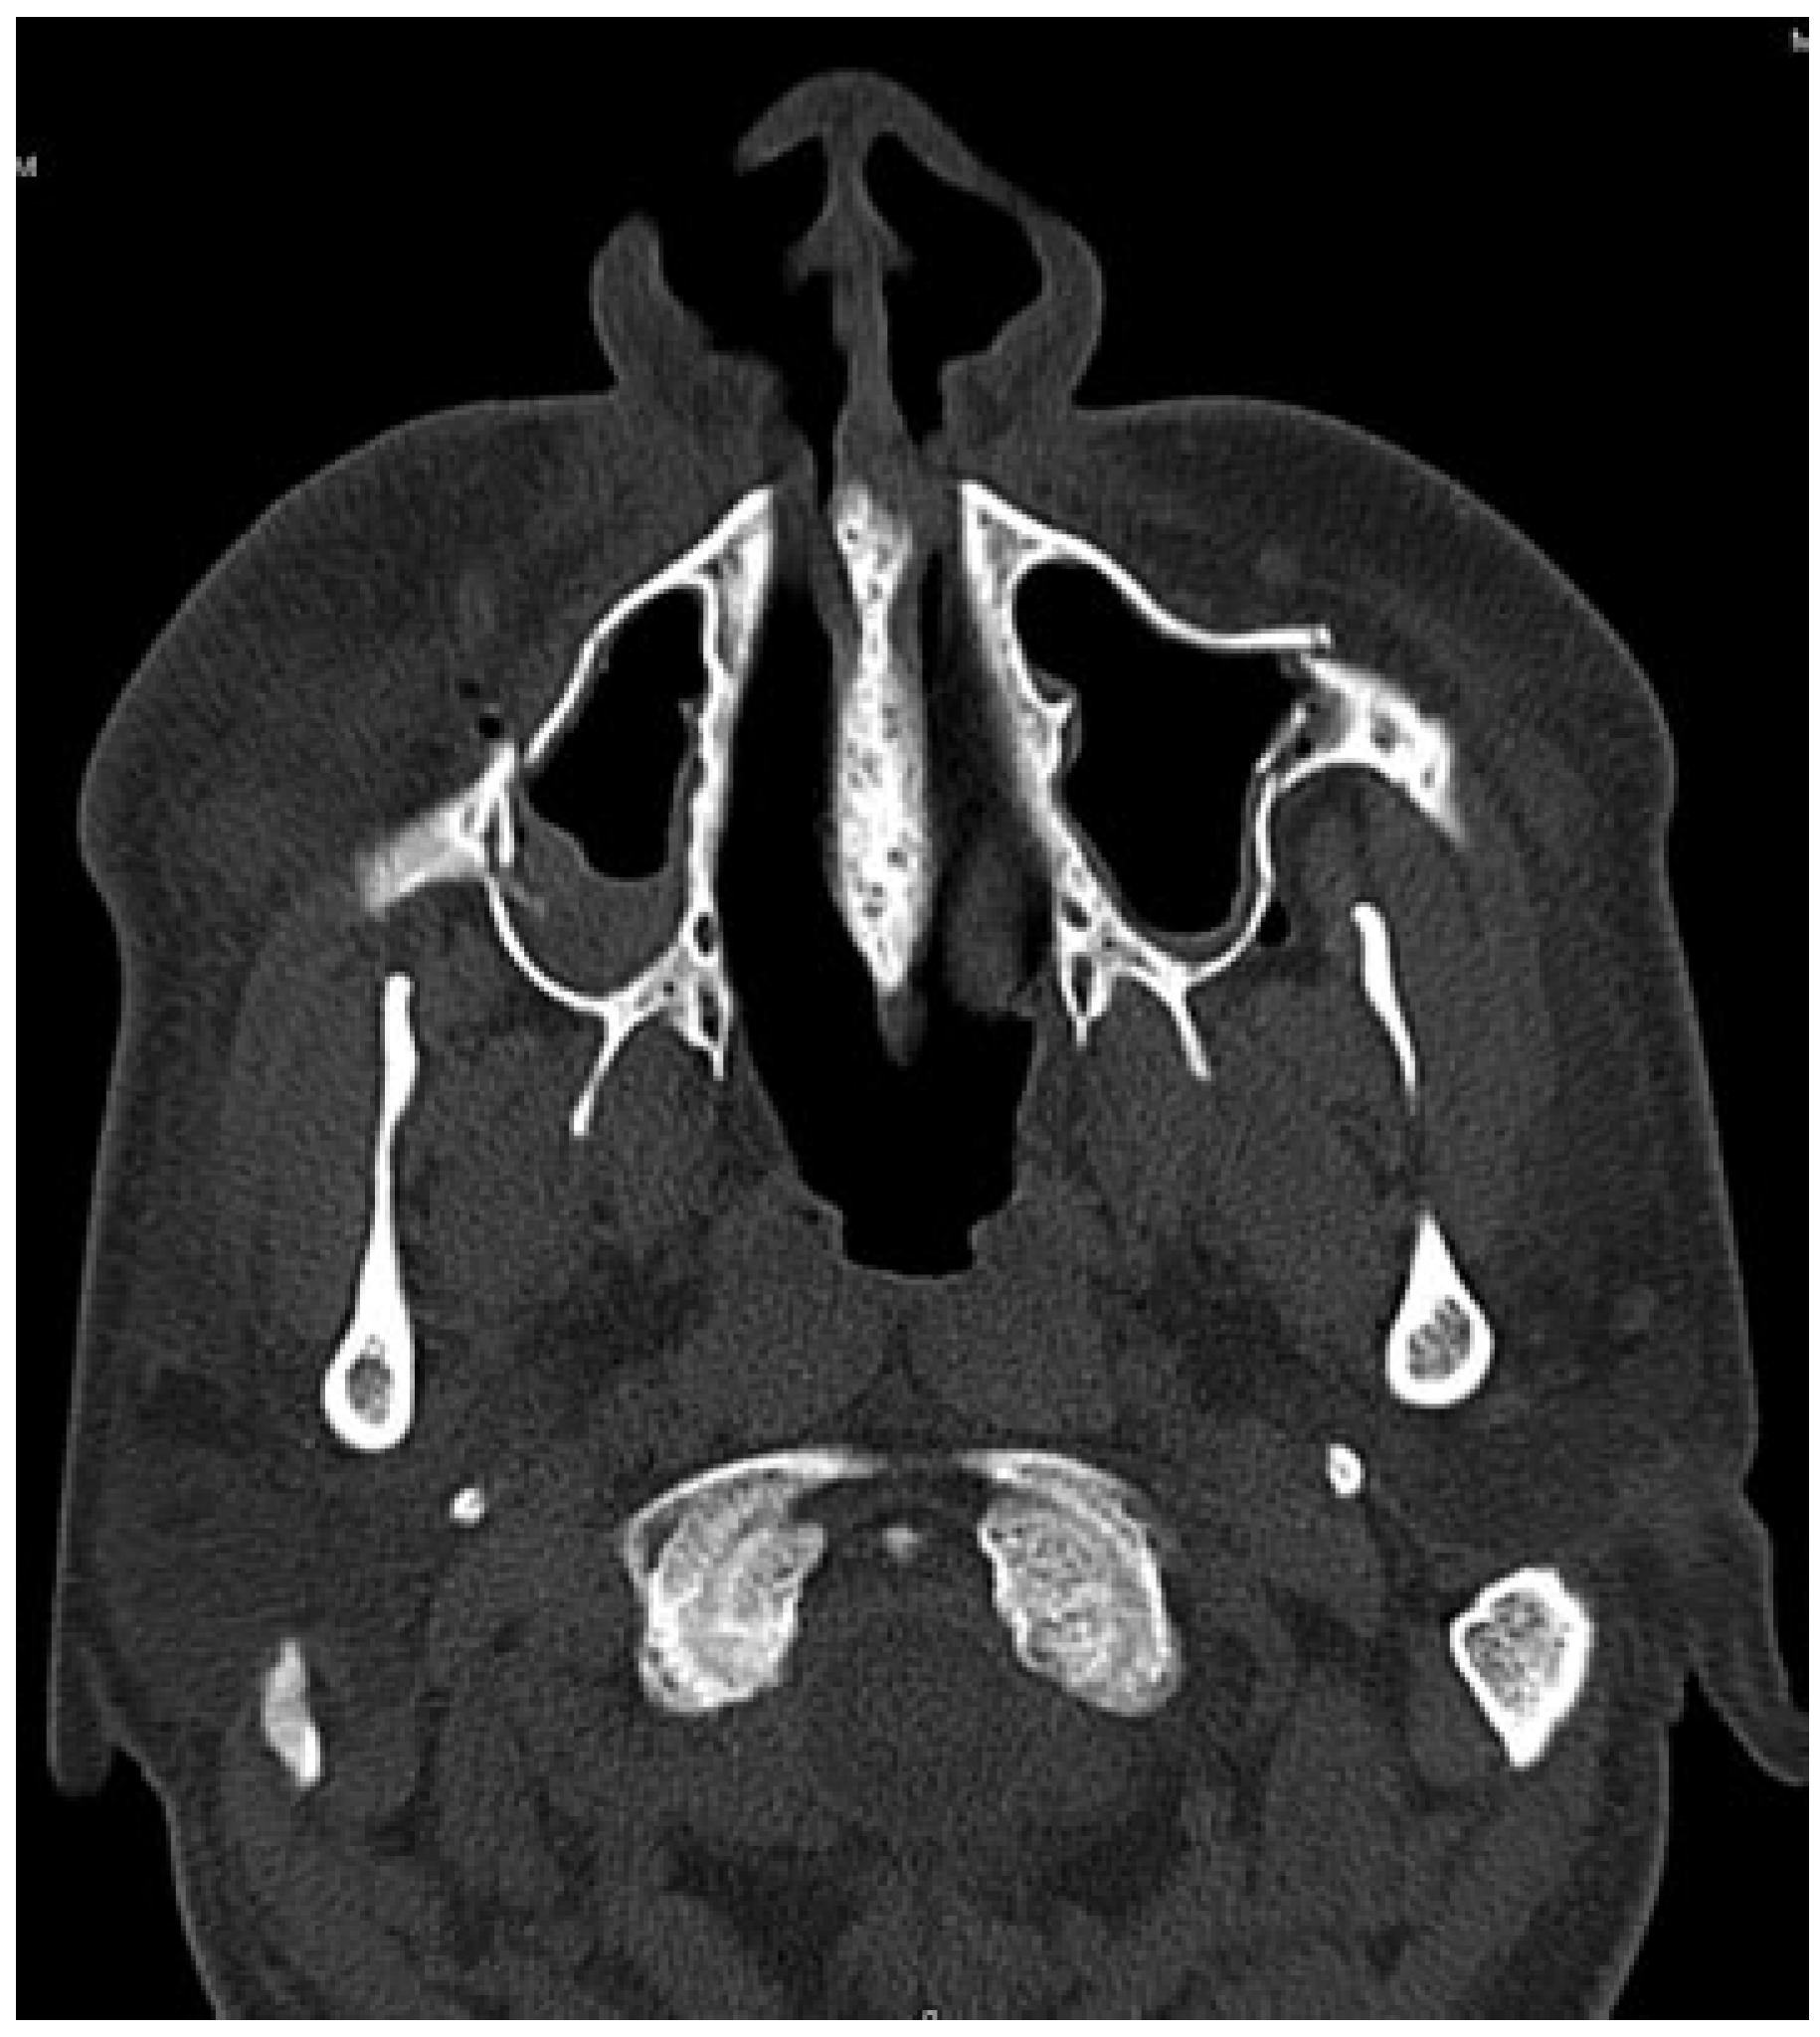

A 35-year-old male patient presented to Accident and Emergency Department with facial injuries associated with RTA. As per the patient, he collided with another motorbike and was not wearing a helmet at the time of accident. On examination, he had bruises on bilateral zygomatic areas and a 2-cm laceration on the right supratarsal fold close to zygomaticofrontal suture. The right and left zygoma were tender on palpation and associated with depression of zygomatic arch areas. Infraorbital paresthesia was present on the right side. Trismus was moderate, and a detailed clinical and computed tomography examination showed displaced bilateral isolated zygomatic complex (Figure 1 and Figure 2) and arch fractures (Figure 3) without any other associated facial bone fractures. He underwent open reduction and internal fixation of both zygomatic complexes including the closed reduction of the arch by Gillies approaches and fixation via an intraoral approach at the Lefort level I (Figure 4). The postoperative recovery was uneventful with good mouth opening and with no cosmetic deficit.

Figure 1. Computed tomography scan showing displaced bilateral isolated zygomatic complex fracture.